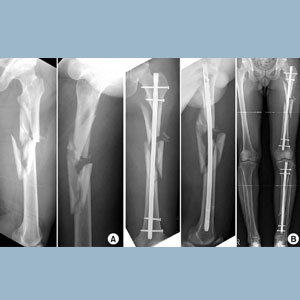

As advancements are made in the prevention of automobile fatalities, an increase...

Read details